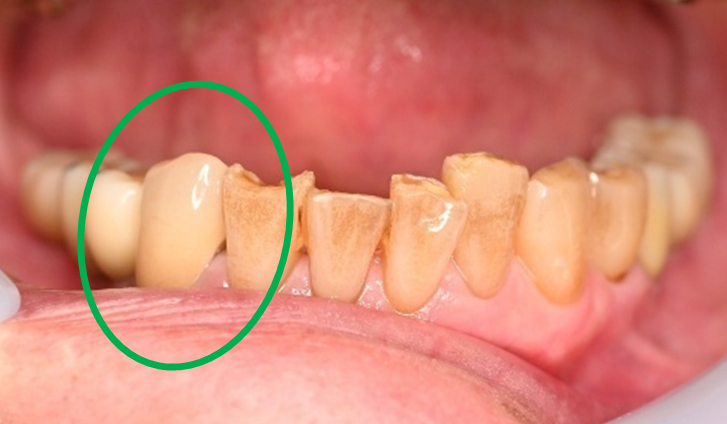

女性 Yさん 60代 (オールセラミック冠)

主訴

以前治療した右下の犬歯が、虫歯になり色が変わってきているので、治したい。

治療内容

根管治療をし、オールセラミック冠を被せました。

所感

神経が取り除かれ、歯自体が変色し、虫歯になっていました。根管治療をし、ファイバーコアを入れ、オールセラミック冠を被せました。

オールセラミック冠1本(失活歯):¥104,500(税込)

Before

After